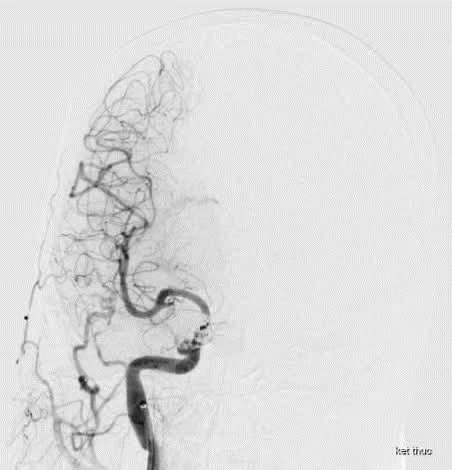

Bác sĩ thực hiện các xét nghiệm bao gồm chụp CT mạch máu não và chụp mạch máu số hóa xóa nền (DSA). Ảnh: BVCC

Sau khi thăm khám, thực hiện các xét nghiệm bao gồm chụp CT mạch máu não và chụp mạch máu số hóa xóa nền (DSA), bệnh nhân được chẩn đoán bị rò động mạch cảnh – xoang hang (Carotid-Cavernous Fistula - CCF).

Bệnh nhân được chẩn đoán bị rò động mạch cảnh – xoang hang. Ảnh: BVCC

Theo các bác sĩ, đây là hiện tượng xuất hiện lỗ rò động tĩnh mạch giữa động mạch cảnh và xoang hang, khiến thay đổi các dòng dẫn lưu máu tại xoang hang.